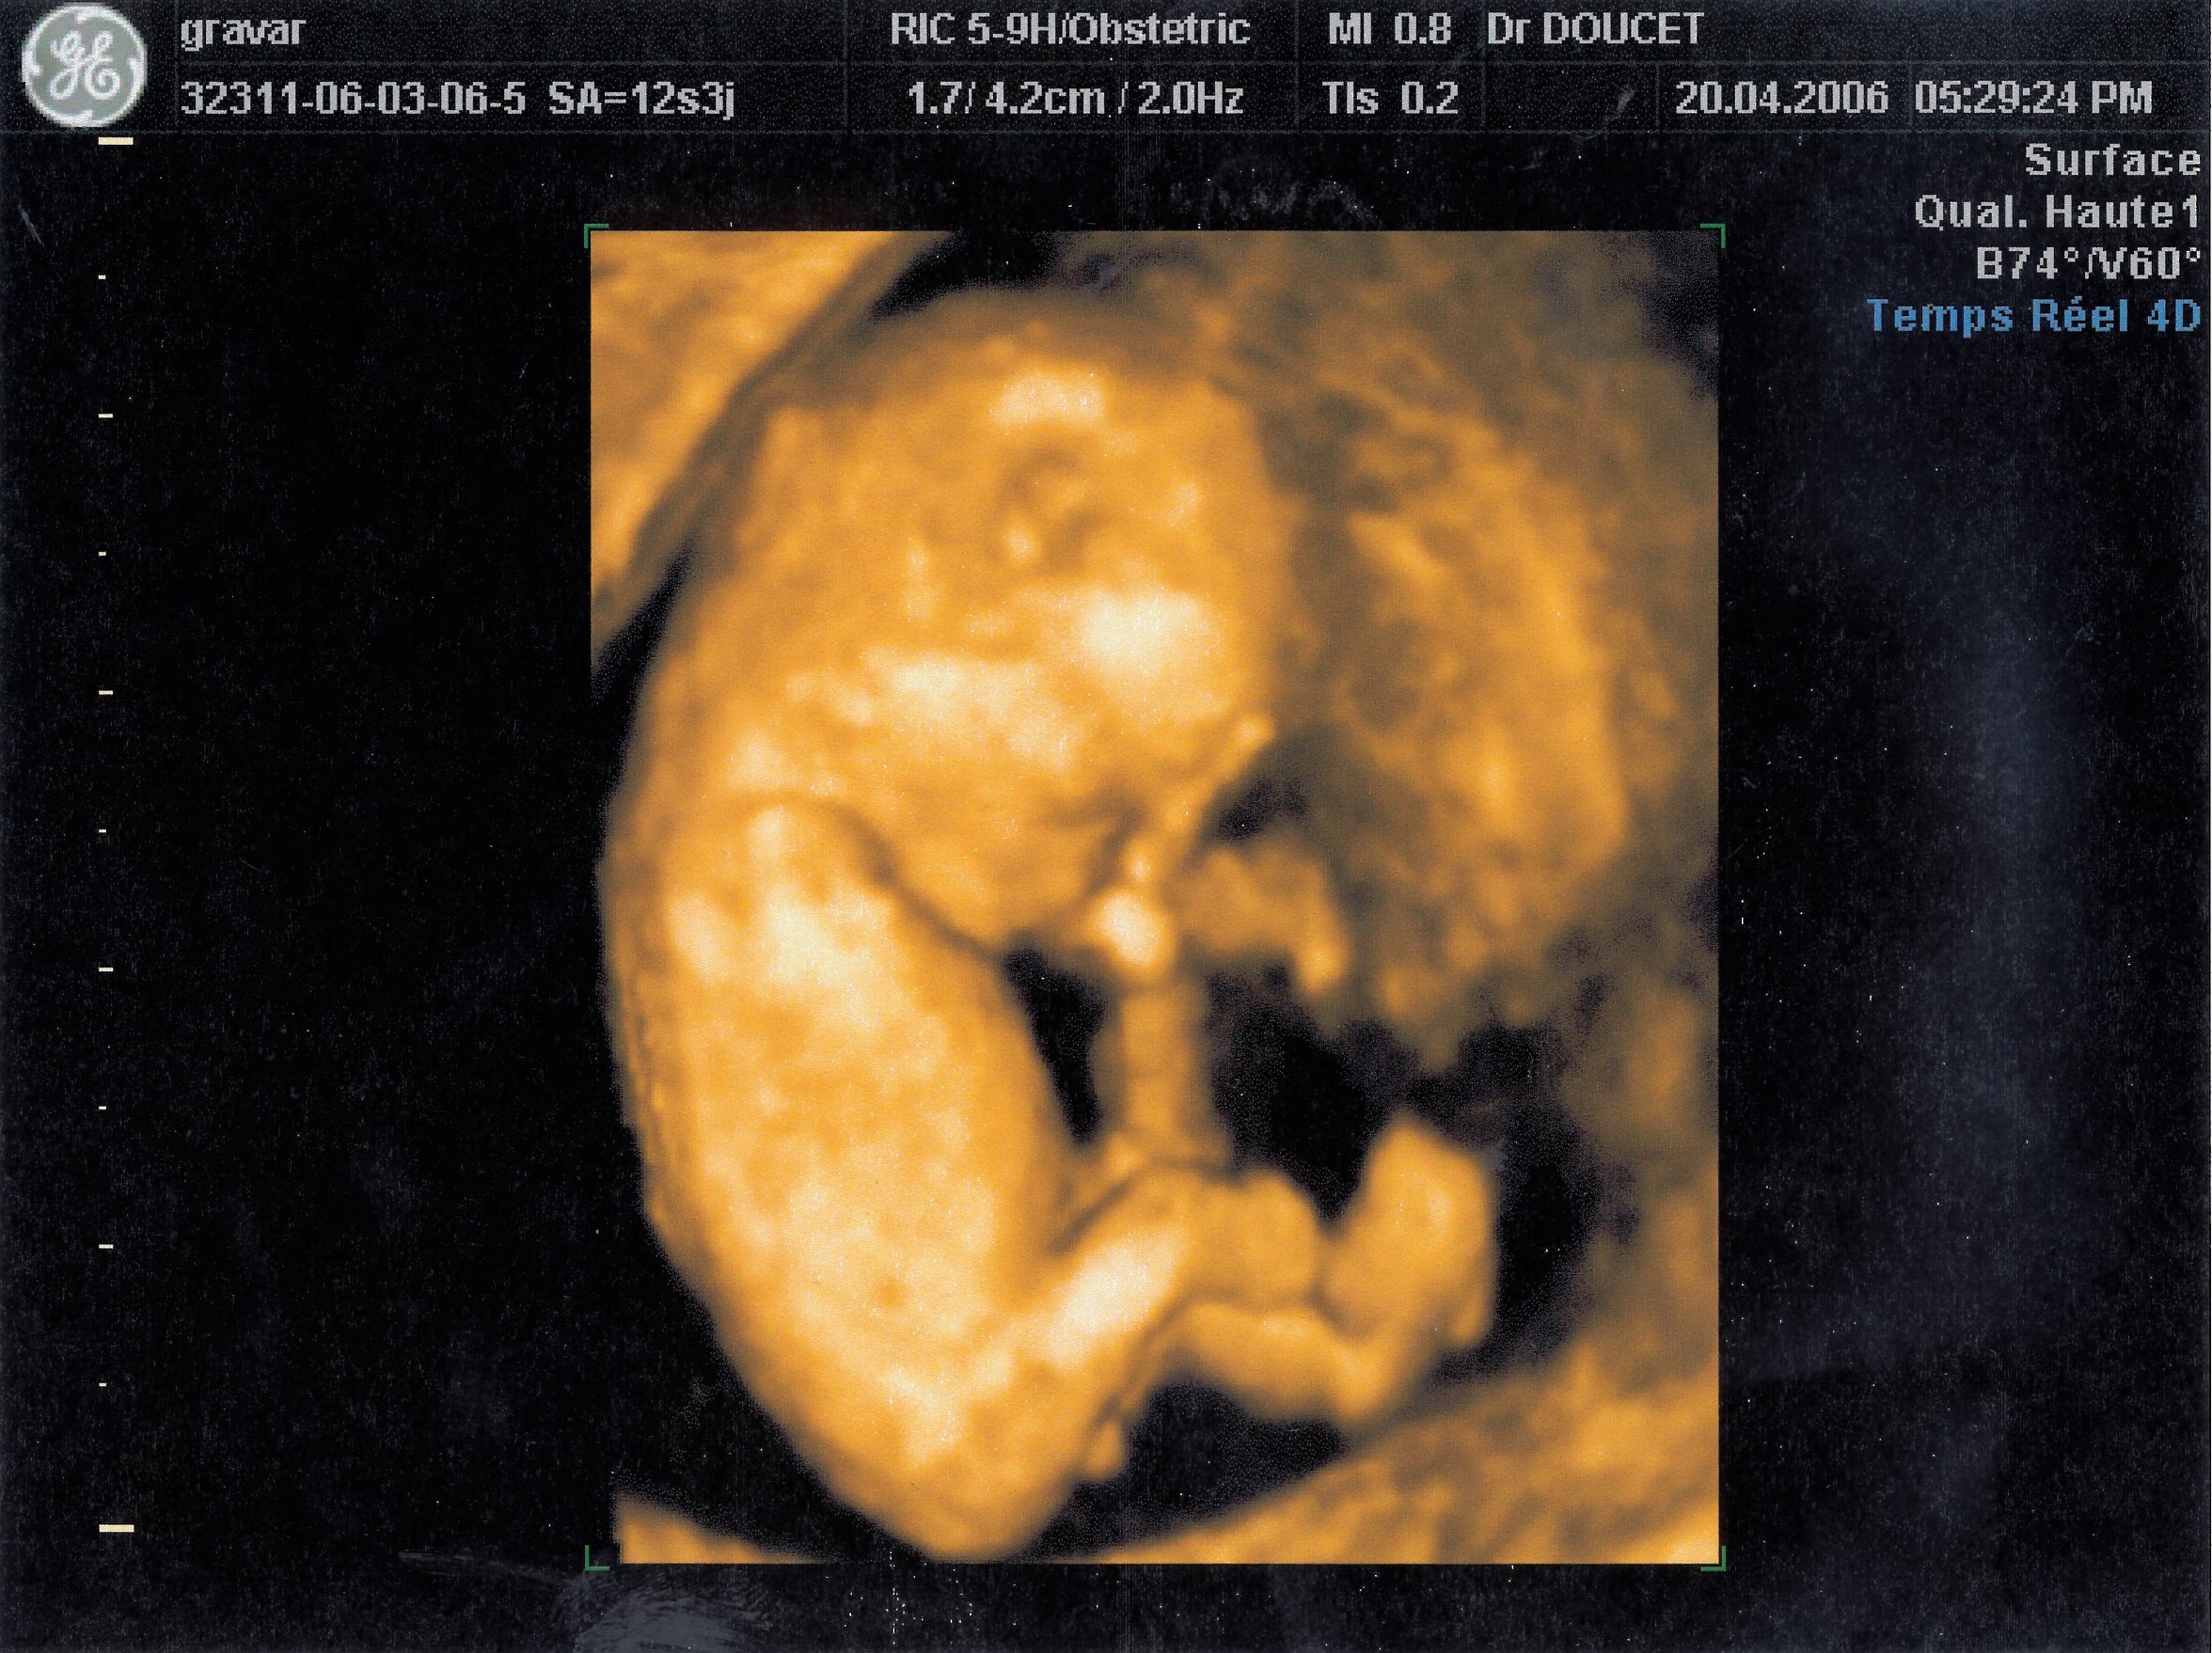

20 avril 2006

A l'intérieur, je ressemble à ceci :